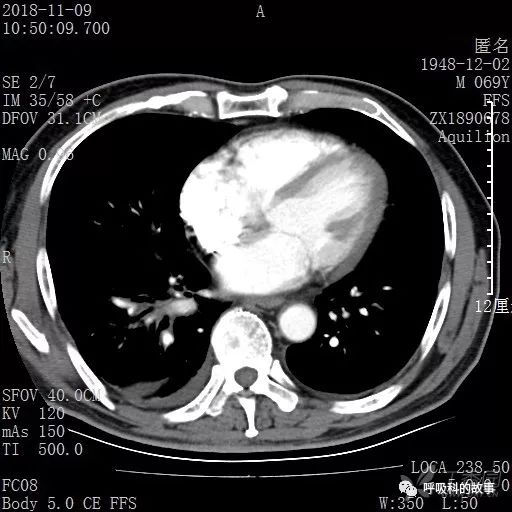

胸部增强CT示右肺门占位伴远端阻塞性肺炎,纵膈、右肺门、右侧颈根部、右侧腋下及肝门部肿大淋巴结。两侧胸腔少量积液。

纵隔窗的增强CT

肺窗CT